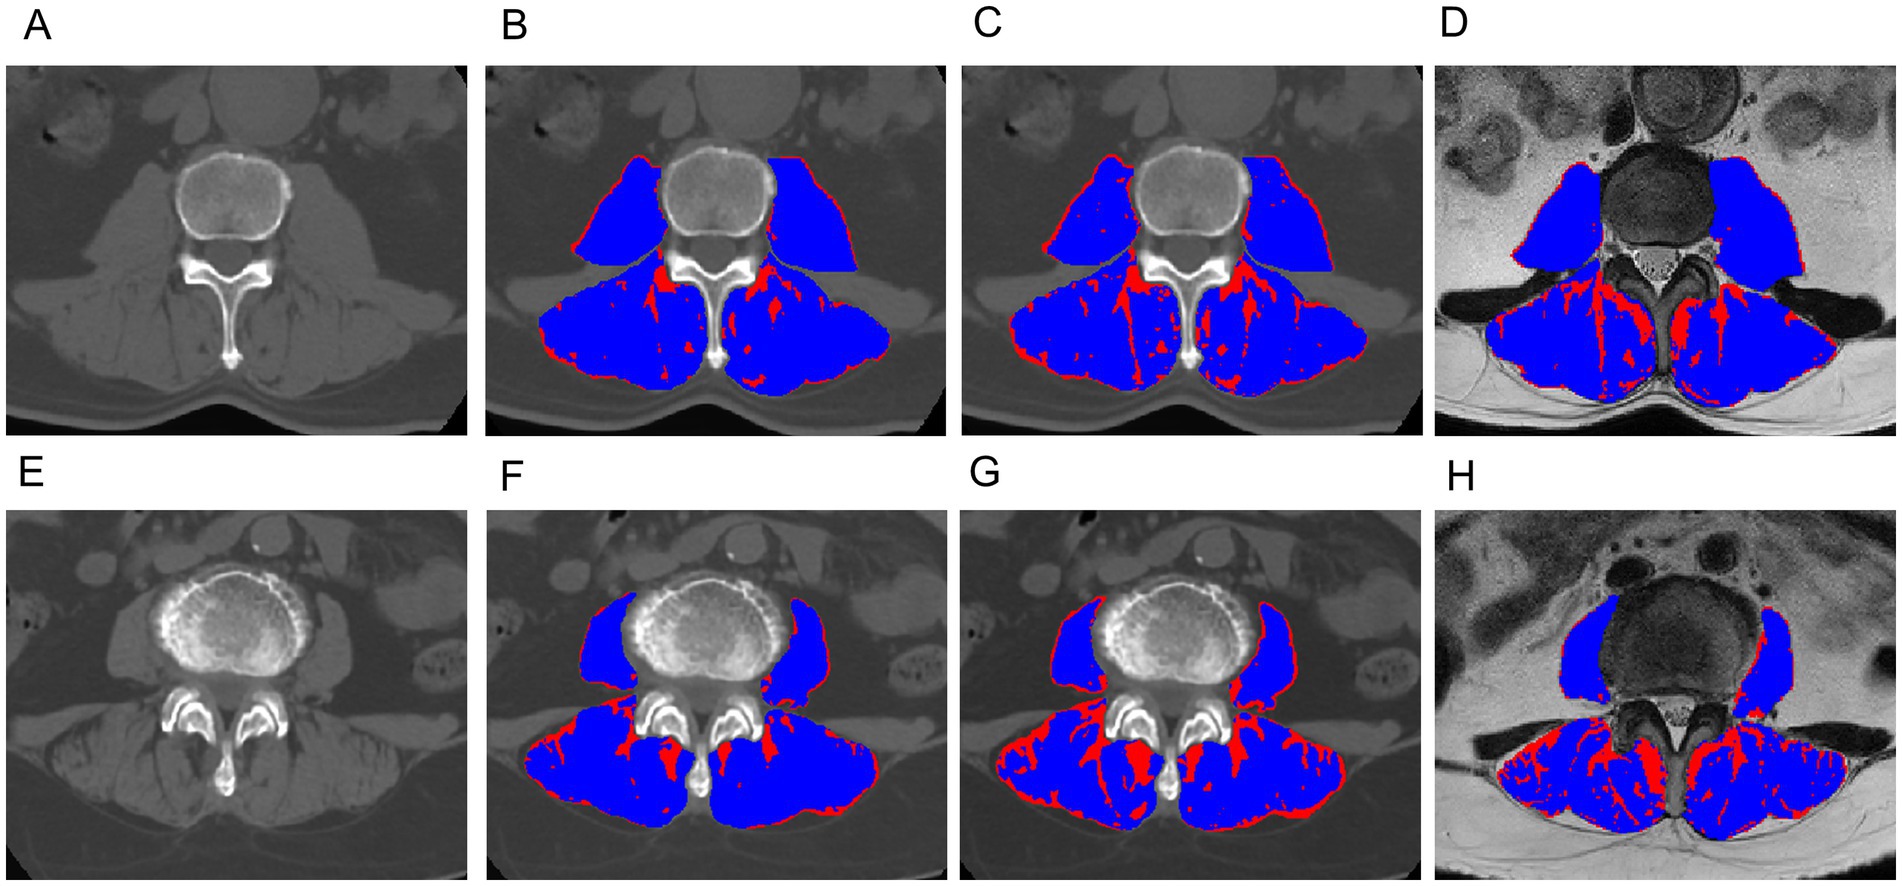

Table 5 presents the comparison of the diagnostic efficiency of different models. In the training set, the CT-based GMM model achieved the highest AUC values (AUC = 0.990), followed by the CT-based Otsu model (AUC = 0.986), the clinical model (AUC = 0.764), the CT-based K-means model (AUC = 0.727), the MRI-based GMM model (AUC = 0.697), the MRI-based K-means model (AUC = 0.649), and the MRI-based Otsu model (AUC = 0.638). In the retrospective validation group, the diagnostic efficiency from highest to lowest was: CT-based Otsu model (AUC = 0.958), CT-based GMM model (AUC = 0.903), the CT-based K-means model (AUC = 0.772) clinical model (AUC = 0.719), MRI-based K-means model (AUC = 0.537), MRI-based GMM model (AUC = 0.537), and MRI-based Otsu model (AUC = 0.528). In the prospective validation cohort, the CT-based Otsu model demonstrated the highest diagnostic efficiency (AUC = 0.819). Figure 4 shows a schematic of the segmentation for the better-performing models, and Figure 5 presents the ROC curves for model comparison. Using five-fold cross-validation on the training set, the CT-based GMM model demonstrated the best stability (average AUC = 0.99), followed by the CT-based Otsu model (average AUC = 0.94). Detailed ROC curves and average AUC values for the five-fold cross-validation are shown in Supplementary Figures S3, S4.

Figure 4. Exemplary slices showing the differentiation between muscle (blue) and fat (red) obtained with the CT-based Gaussian Mixture Model (B,F), CT-based Otsu thresholding method (C,G) and MRI-based Otsu thresholding method (D,H), (A–D): A 62-year-old male with sarcopenia; (E–H): an 66-year-old female without sarcopenia. The AUC of the CT-based Gaussian Mixture Model and the Otsu model for predicting sarcopenia was 0.98 and 0.93, respectively. The AUC of the Gaussian mixture model and the Otsu model for predicting sarcopenia was 0.990 and 0.986, respectively.